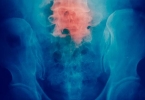

宫颈肥大增生通常不会直接癌变,但需警惕其发展为宫颈癌的风险。宫颈肥大增生的主要原因是慢性炎症、激素水平异常、多次分娩、宫颈损伤以及宫颈息肉等因素。宫颈肥大增生本身属于良性病变,但若长期存在炎症刺激或合并高危型人乳头瘤病毒HPV感染,可能增加癌变风险。